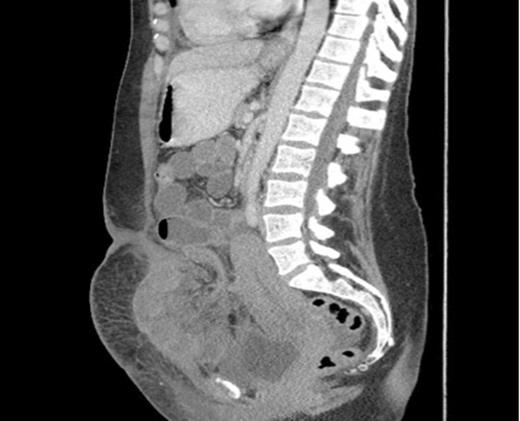

Sagittal section showing dilated loops of small bowel and a segment of small bowel adherent to the anterior abdominal wall.

The next day she became pyrexial (38°C) and tachycardic (103 bpm). Examination revealed a tender abdomen, with guarding and absent bowel sounds. Her neutrophilic leukcytosis increased from 13 to 27 and CRP increased to 159. She was commenced on gentamicin and a CT abdomen/pelvis was ordered. Radiology reported a high-grade acute SBO secondary to herniation of segment of small bowel into anterior abdominal wall defect. A laparotomy was performed and revealed a segment of strangulated small bowel lying above the rectus muscles and trapped beneath the intact rectus sheath. 34cm of necrotic small bowel was resected and an end to end anastomosis was fashioned. The patient made a good post-operative recovery and was discharged 9 days later.